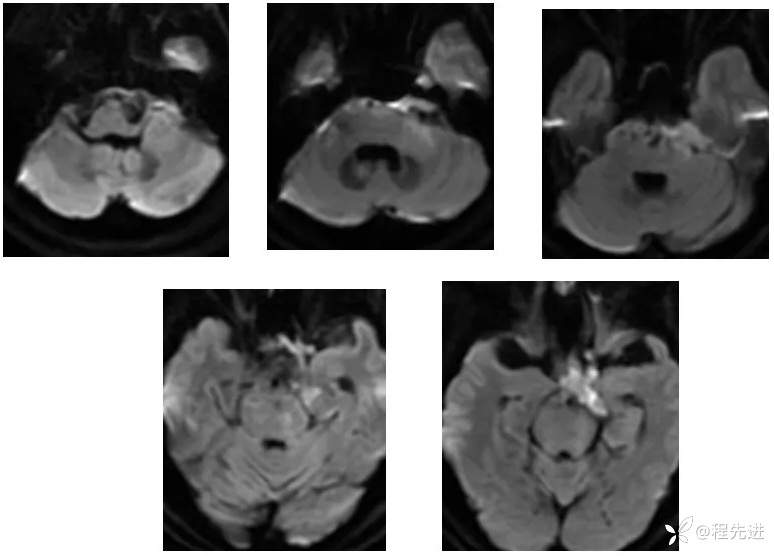

【现病史及既往史】:右眼斜视及视力下降7个月,右眼脸下垂3个月,右眼失明1个月

查体:生命体征平稳,右眼脸下垂,右眼失明,左眼内收位,外展受限,光反应迟钝,左侧角膜反射减弱,左侧听力下降,左面部痛温觉减弱无吞咽困难,无饮食饮水呛咳,伸舌舌尖左偏。